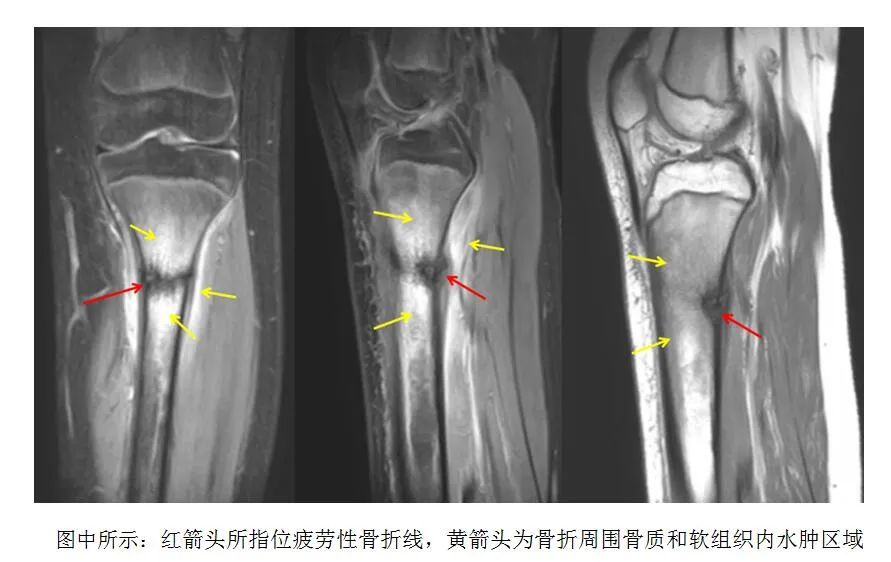

前不久,一名女孩因“右膝關節(jié)疼痛”到漯河市骨科醫(yī)院(漯河醫(yī)專二附院)就診,經(jīng)過MRI檢查發(fā)現(xiàn),她右側脛骨上段大片骨髓水腫,并伴有局部細微骨折線,最終被診斷為疲勞性骨折。

在出現(xiàn)癥狀的初期如果我們去醫(yī)院拍攝X線片或CT,可能會無明顯異常發(fā)現(xiàn),往往持續(xù)發(fā)展到較嚴重時期才可以在X線檢查中發(fā)現(xiàn)異常。因此,早期當臨床疑有疲勞骨折,而X線片或CT檢查無明顯異常時,可考慮采用磁共振(MRI)檢查,發(fā)病早期即可發(fā)現(xiàn)骨折區(qū)域水腫信號以及骨折線出現(xiàn)。